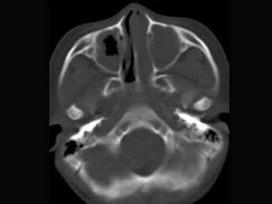

男,7岁,无意发现鼻腔肿物,无明显症状,CT如图所示,最可能诊断为 ( )

• A.鼻炎鼻息肉

答案: A